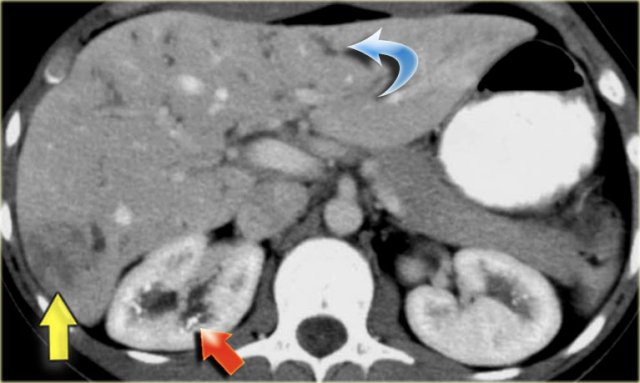

The patient on the left developed severe liver failure and a resection was performed.

Notice the intrahepatic bile duct dilatation, splenomegaly and dilated venous collaterals.

In the resected specimen there is a central dot sign (blue arrow) and a small pus collection (yellow arrow).